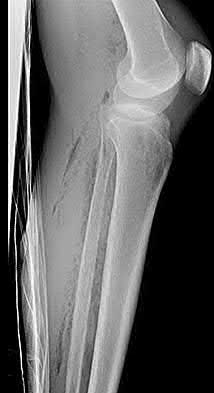

A 28-year-old male sustains a closed comminuted tibial shaft fracture.

Two hours post-injury, he develops severe leg pain unyielding to narcotics. His blood pressure is 120/80 mmHg. Intracompartmental pressure monitoring is performed. Based on current guidelines, which measurement dictates an emergent 4-compartment fasciotomy?

Explanation

Acute compartment syndrome is classically defined by tissue hypoperfusion. The absolute compartment pressure is less reliable than the differential pressure (Delta P). A Delta P (Diastolic Blood Pressure minus Compartment Pressure) of less than 30 mmHg is an absolute indication for emergency fasciotomy, as capillary perfusion gradient is lost when tissue pressure approaches the diastolic pressure.